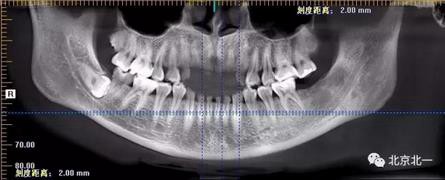

圖一:CBCT顯示右側下頜水平骨埋伏牙,牙冠距離下牙槽神經管接近。

圖二:自帶的CBCT顯示下牙槽神經管貼著智齒走形。

圖三:截面圖顯示神經管位置。